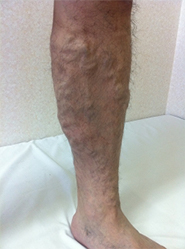

動脈は心臓から押し出された勢いで血液が流れていきますが、静脈にはそのような勢いがありません。筋肉の収縮と静脈に存在する逆流防止弁(一方弁)によって全身の組織から血液を心臓に戻します。その弁が種々の原因によって壊れてしまうことで、静脈血の逆流を引き起こし、静脈が瘤化していまったものを下肢静脈瘤と言います。軽症である無症状のものから、足がつりやすい、むくむ、痛いなどの症状を伴う中程度のもの、皮膚に湿疹や潰瘍ができる重症のものまであります。

当院では、最新式の下肢静脈瘤に対するレーザー治療機器ELVeSレーザー1470を使用しています。高周波治療でも治療効果はこの機器と同等と言われています。基本的には下肢静脈超音波検査、下肢単純CT撮影で手術適応、手術術式を決定しています。必要な場合には適宜検査を追加いたします。

治療法としては以下のものが考えられます。

• 弾性ストッキング:下肢の血液がうっ滞しないよう弾性ストッキングを着用します。

• 硬化療法:血管内に薬を注入し、瘤の拡大を防ぎます。

• 手術:弁が壊れてしまった静脈を抜去したり、静脈瘤を切除したりします。

• レーザー治療:静脈の内腔をレーザーにて閉塞させ、治療します。

2013年6月から、血管内レーザー治療を行っています。